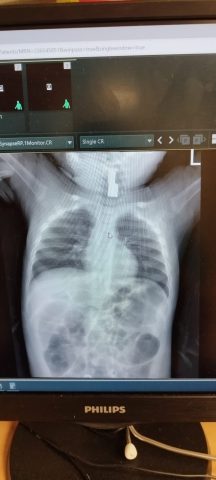

ד"ר רבקה גלעד ממחלקת ילדים הציעה לעשות לזאב צילום חזה, גם כדי להשלים את מכלול הבדיקות הרפואיות ולהרגיע את ההורים המודאגים."כשקיבלתי את תוצאות הצילום הייתי מופתעת בעצמי. התינוק היה כל כך חיוני, וממש לא ציפיתי לראות גוף זר, ובטח שלא כל כך גדול, בצילום שלו", מספרת ד"ר גלעד. "ההחלטה להפנות אותו לצילום נקבעה באמת על סמך תחושה, שעדיין לא מיצינו את כלל הבדיקות. המחשבה על מה היה יכול לקרות אם לא היינו עושים צילום – מטלטלת אותי בכל פעם שאני חושבת על המקרה".

ד"ר גלעד התקשרה מיד לרופא אף אוזן גרון – ד"ר אחמד סיאג' אשר חבר אליה לטיפול בתינוק. הוא זיהה בצילום גוף זר במרקם מתכתי, הכניס לזאב מצלמה שנכנסת דרך האף ויורדת לגרון – וראה משהו בוהק שמסתיר את מיתרי הקול. "לא יכולתי לראות את דרכי הנשימה של התינוק, והבנתי שהוא במצב מסכן חיים.

הרופאים ביצעו לזאב צילום חזה נוסף כדי לראות אם הגוף הזר השאיר נזקים בוושט, ולמזלו הגדול, מלבד פצעים קטנים – הוא יצא בריא ושלם מן האירוע, לא העלה חום וחזר לישון ולינוק. הוא נשאר להשגחה ללילה והשתחרר בבוקר שלמחרת, כשהוא רגוע ומחייך.

אנו יודעים שמדובר באחד הפחדים הגדולים ביותר עבור הורים, ולכן גם כשהבית מתנהל באחריות ובדאגה טבעית לתינוקות ופעוטות וגם כששמים 4 עיניים – עדיין נדרשת הקפדה יוצאת דופן כדי למנוע מקרים כאלה, שתוצאותיהם עלולות להיות הרות אסון. כמובן, שגם אם נזהרנו מאוד והקפדנו להרחיק תינוקות מאותם חפצים אבל אנחנו נתקלים בהשתנקות יוצאת דופן או ניסיון להקיא עצם כלשהו ובשינוי התנהגותי שמעיד על מצוקה מסוימת, יש לגשת לבדיקה רפואית באופן מיידי". בתמונות, זאב בן ה-9 חודשים, הדמיית החלק המתכתי והחלק שנשלף בחדר הניתוח. הדר אלבויםדוברת הדסה